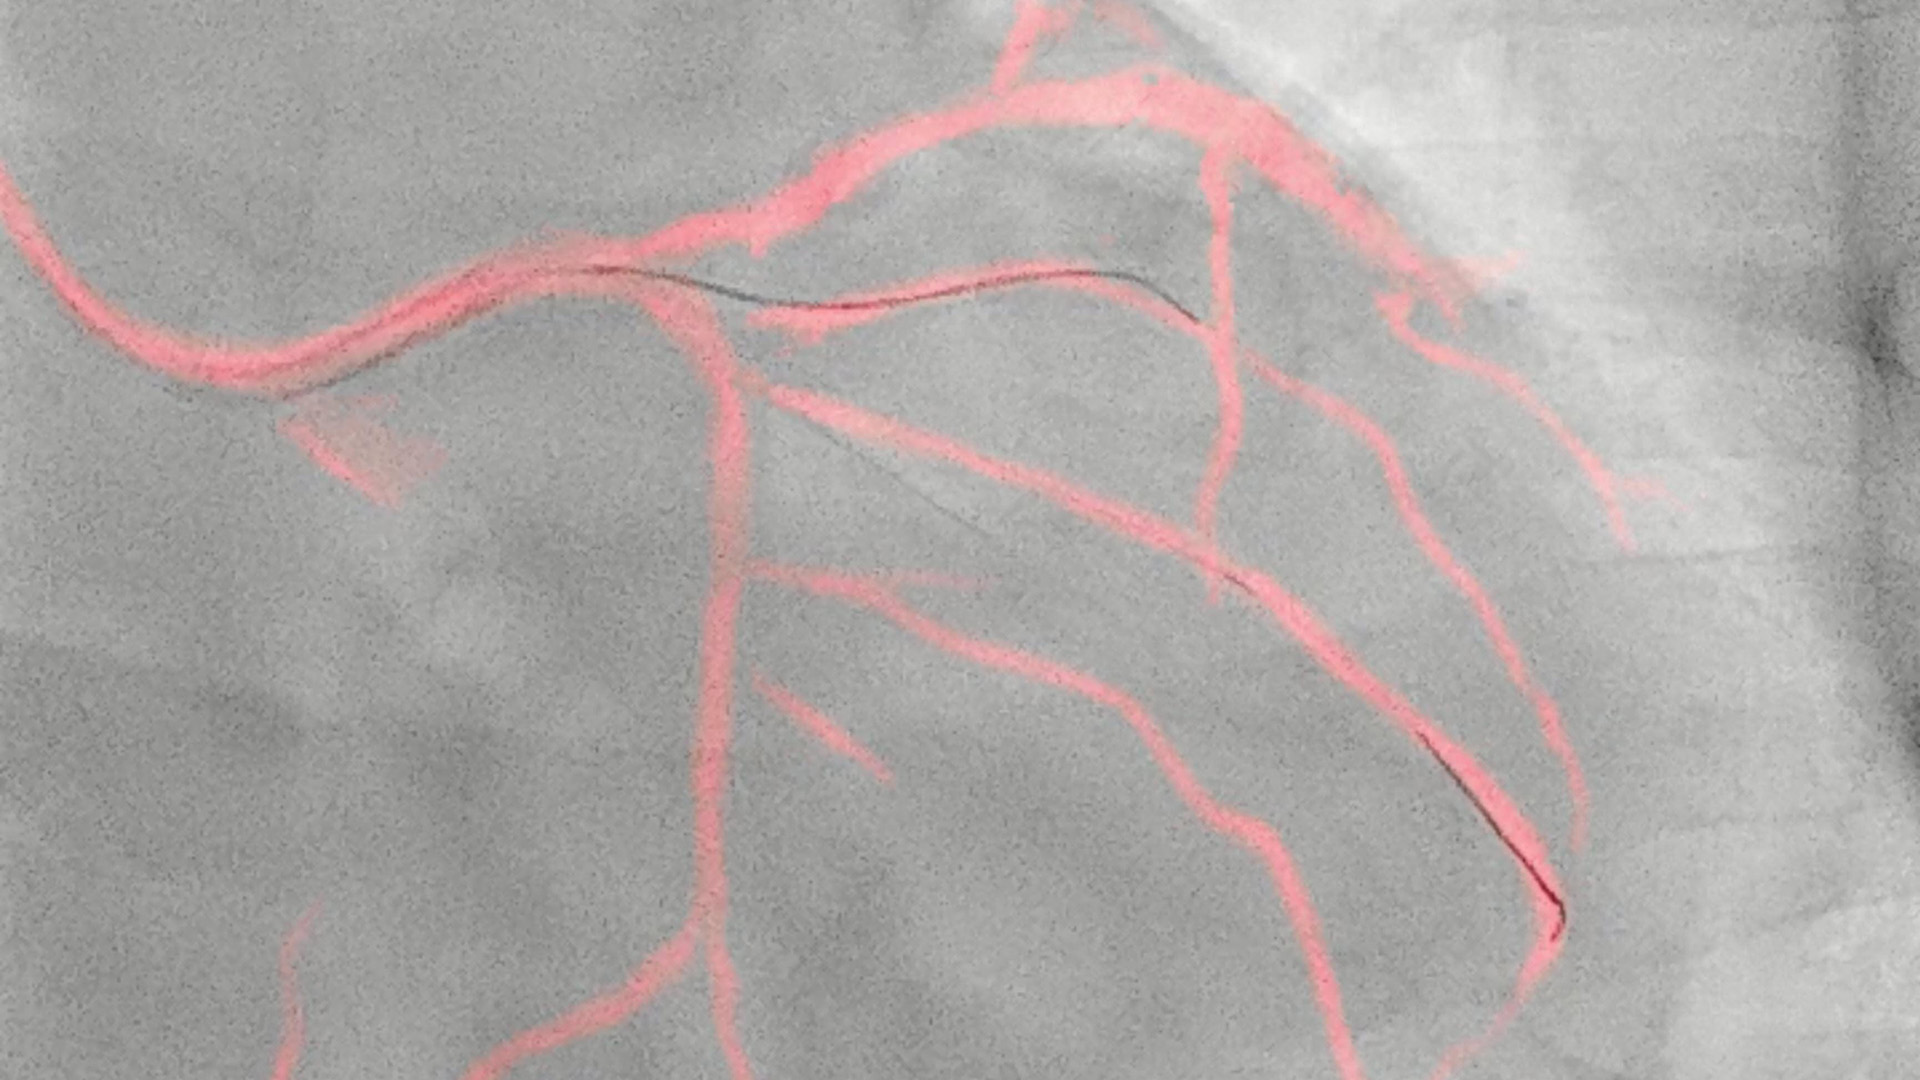

• Philips’ image-guided navigation increases safety during coronary interventions and reduces the use of contrast media by an average of 28.8%

Philips’ image-guided navigation increases safety during coronary interventions and reduces the use of contrast media by an average of 28.8%